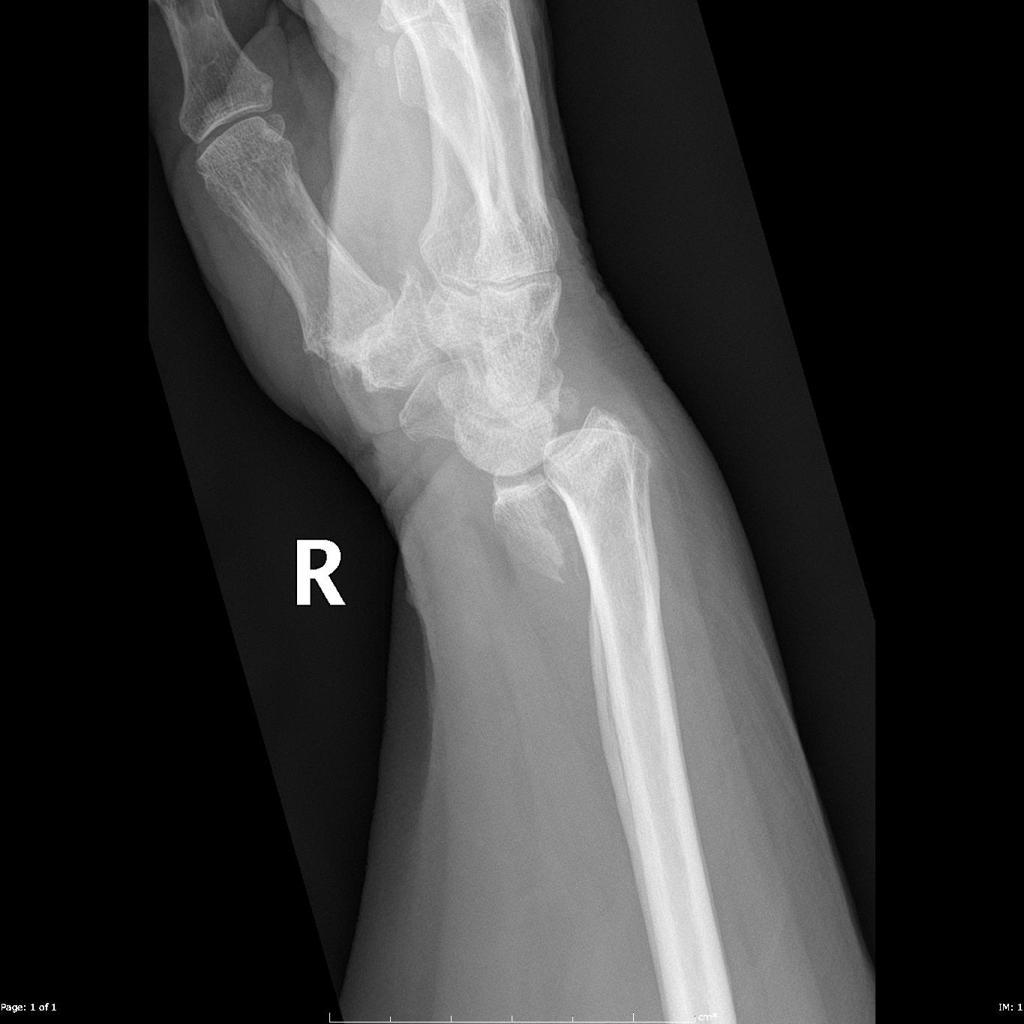

Fracture of the radius and dislocation of the ulna at the distal radioulnar joint

Whith any radial shaft fracture, which investigation is mandatory and why?

Lateral X-ray of the wrist

(in case of Galeazzi fracture dislocation)

How are Galeazzi fractures treated?

ORIF

A _________ fracture involves fracture of the ulnar shaft and dislocation of the proximal radial head at the elbow, whilst a __________ fracture involves a fracture of the radial shaft alongside dislocation of the ulna at the distal radio-ulnar joint

A Monteggia fracture involves fracture of the ulnar shaft and dislocation of the proximal radial head at the elbow, whilst a Galeazzi fracture involves a fracture of the radial shaft alongside dislocation of the ulna at the distal radio-ulnar join